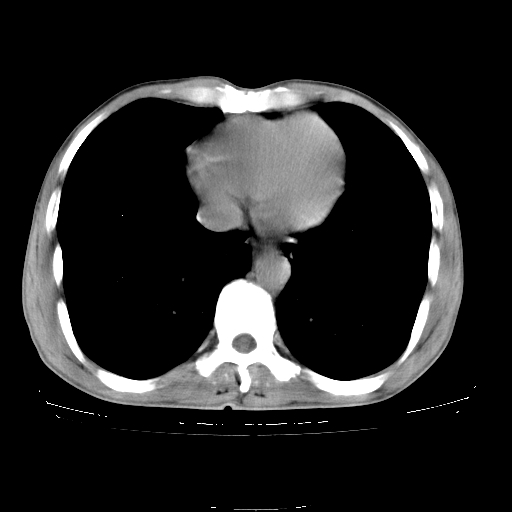

以下是引用yangyudong333在2008-4-29 5:38:00的发言:[br]比较典型的矽肺结节.支持[br]诊断依据:[br] 1.x线表现:[br] ①典型矽肺为多发直径 1~3mm 小结节,即矽结节,由胶原纤维和硅尘构成,可融合成团块,好发于上肺。[br] ②团块周围常有肺大泡。[br] ③胸内淋巴结增大、钙化。如肺门淋巴结呈蛋壳样钙化有助于与其他尘肺区别。[br] ④胸膜常广泛粘连、增厚。[br] 2.ct表现[br] ①两肺散在大小较为一致的小结节影,其密度较高,边界清楚。[br] ②小结节可融合为较大团块影,直径约 1cm ,甚至可达 10cm以上,易发生在上叶。[br] ③小结节周围常并有小叶中心气肿或弥漫性肺气肿。

以下是引用liuyue在2008-4-28 22:30:00的发言:[br]比较典型的矽肺结节.[br]请结合临床及化验除外矽肺合并肺结核之可能.